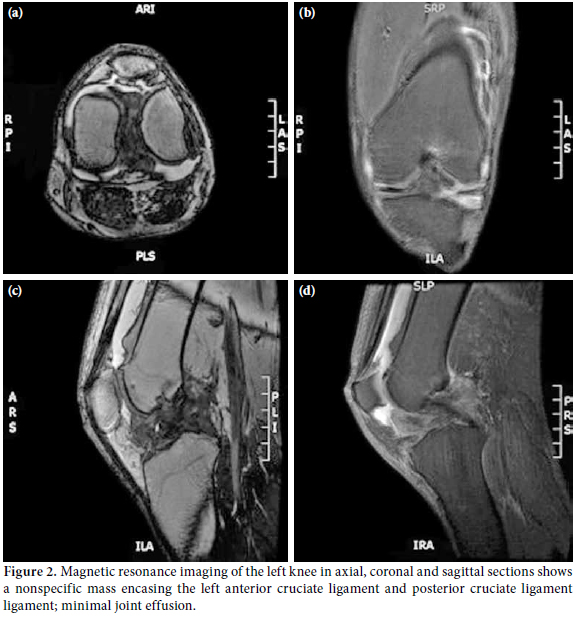

Laboratory investigations were unremarkable with the exception of elevated uric acid levels (611 umol/L). A plain radiograph of the left knee showed no abnormalities (Figure 1). Subsequently, magnetic resonance imaging (MRI) was ordered to determine the cause of the locked knee, and it showed minimal joint effusion with a hypointense soft tissue mass encasing the anterior cruciate ligament (ACL) and posterior cruciate ligament (PCL) measuring 5.7x1.5x2.2 cm. The MRI of the left knee in the axial, coronal, and sagittal sections revealed a nonspecific mass encasing the left ACL and PCL ligament with minimal joint effusion, which was suggestive of a synovial sarcoma of the left knee joint (Figure 2).

Gout was not considered as the provisional diagnosis in this case due to the following reasons: 1. Intraarticular tophi lack obvious clinical presentation; 2. The majority of patients with intraarticular gout would have had a history of gout for 10-12 years before the appearance of radiographic lesions or physical findings (Our case was only diagnosed five years previously.); 3. Though it's a rare finding, calcification within the tophi is one of the radiological diagnostic criteria for gout (not present in our case); and 4. The MRI showed a nonspecific enhancement which is not suggestive of gouty tophi.[1]